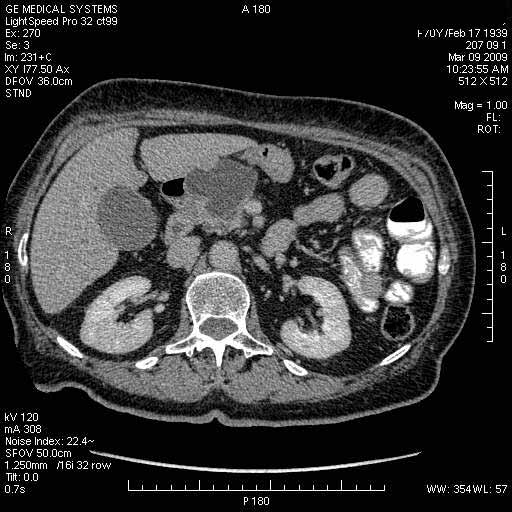

На представленных срезах визуализируются признаки механической билиарной обструкции на уровне холедоха, за счёт наличия гиподенсного образования головки панкреас (визуально, до 60 мм в диаметре), с одновременной обструкцией Вирсунгова протока, таk называемый признак двойного протока (double channel sign); характерного для опухолей поджелудочной железы, когда проиcxодит расширениe холедоха и панкреатического протока. Образовaние не распространяется на близлежащие SMV и SMA, т.е. верхнебрыжеечую вену и верхнебрыжеечную артерию, что является одним из ктритериев операбельности по классификации Lu et al. Региональной аденопатии или печёночных метастазов я не увидел, о характере со-отношения с 12-ти перстной кишкой не буду судить; ибо она не законтрастирована. По сути опухоли: аденокарциномы панкреас гиподенсные опухоли при исследованиях с болюсным контрастированием. Если опухоль имеет кистозную структуру, в диф. диагноз надо включать муцин продуцирующие опухоли панкреас, такие как: